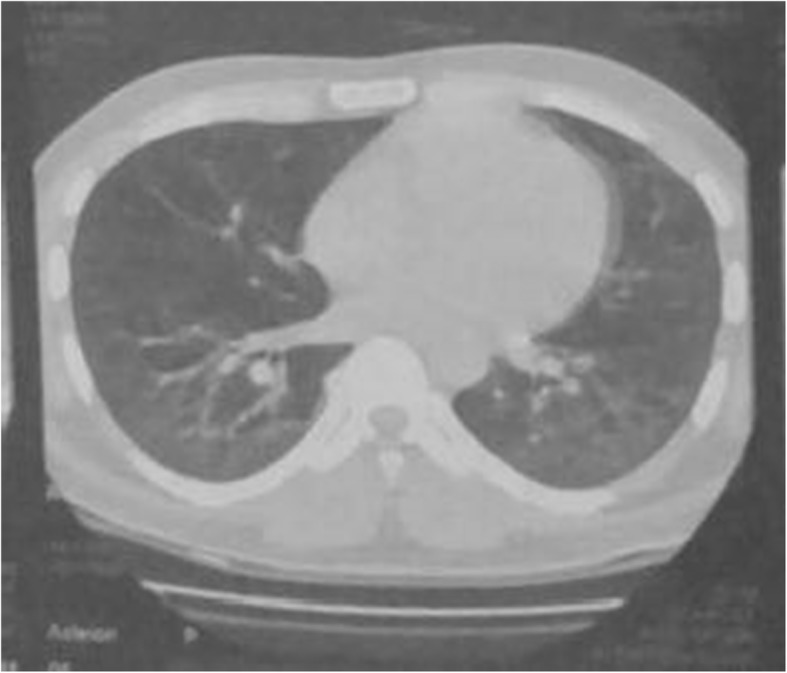

A 27-year-old Pakistani, Asian man, a medical student, with no previous comorbidities and no past history of tobacco smoking and alcohol intake, presented with 3 months’ history of frequent bouts of lower respiratory tract infections associated with exertional dyspnea, arthralgias, gradual weight loss, low grade fever, easy fatigability, and anorexia. His family history was also insignificant for any respiratory or other systemic pathology. In the fourth month of his illness, his fever became high grade associated with profuse sweating. All the baseline investigations were carried out on an out-patient basis. His white cell count was raised and a chest X-ray showed basal consolidation. A suspicion of pneumonia was made and he was started on broad-spectrum antibiotics. His condition improved temporarily but the symptoms re-emerged after a few days. He also received a course of orally administered fluoroquinolones but there was no improvement. A subsequent high resolution computed tomography (HRCT) scan of his chest revealed bilateral ground-glass haziness with areas of traction bronchiectasis, more so in the posterior basal segments of both lower lobes, suggestive of ILD (Figs. 1 and 2). He was given dexamethasone which improved his respiratory symptoms. In the sixth month of illness, he developed progressive proximal muscle weakness. He had difficulty in rising up from a chair and had difficulty in rising up from a squatting position. Throughout this period he had progressive weight loss (19 kg lost in 2 months) and profuse sweating. He was admitted to our hospital and thoroughly investigated. With time his proximal muscle weakness became severe and defined. It now involved his upper limbs as well and he had difficulty in combing his hair. He also gave a history of painful and cyanosed finger tips in winter.

Fig. 1.

CT scan showing features suggestive of Interstitial Lumg Disease (ILD)